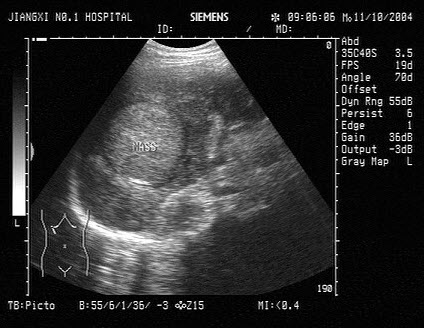

4、单项选择题

患者男52岁,皮肤、巩膜黄染进行性加重,上腹部胀痛不适1个月余,B超检查,胰管扩张,如图所示,根据超声声像图,诊断为()

A.胆总管下段癌

B.肝门部胆管癌

C.壶腹部癌

D.胆总管下段结石

E.胰头癌